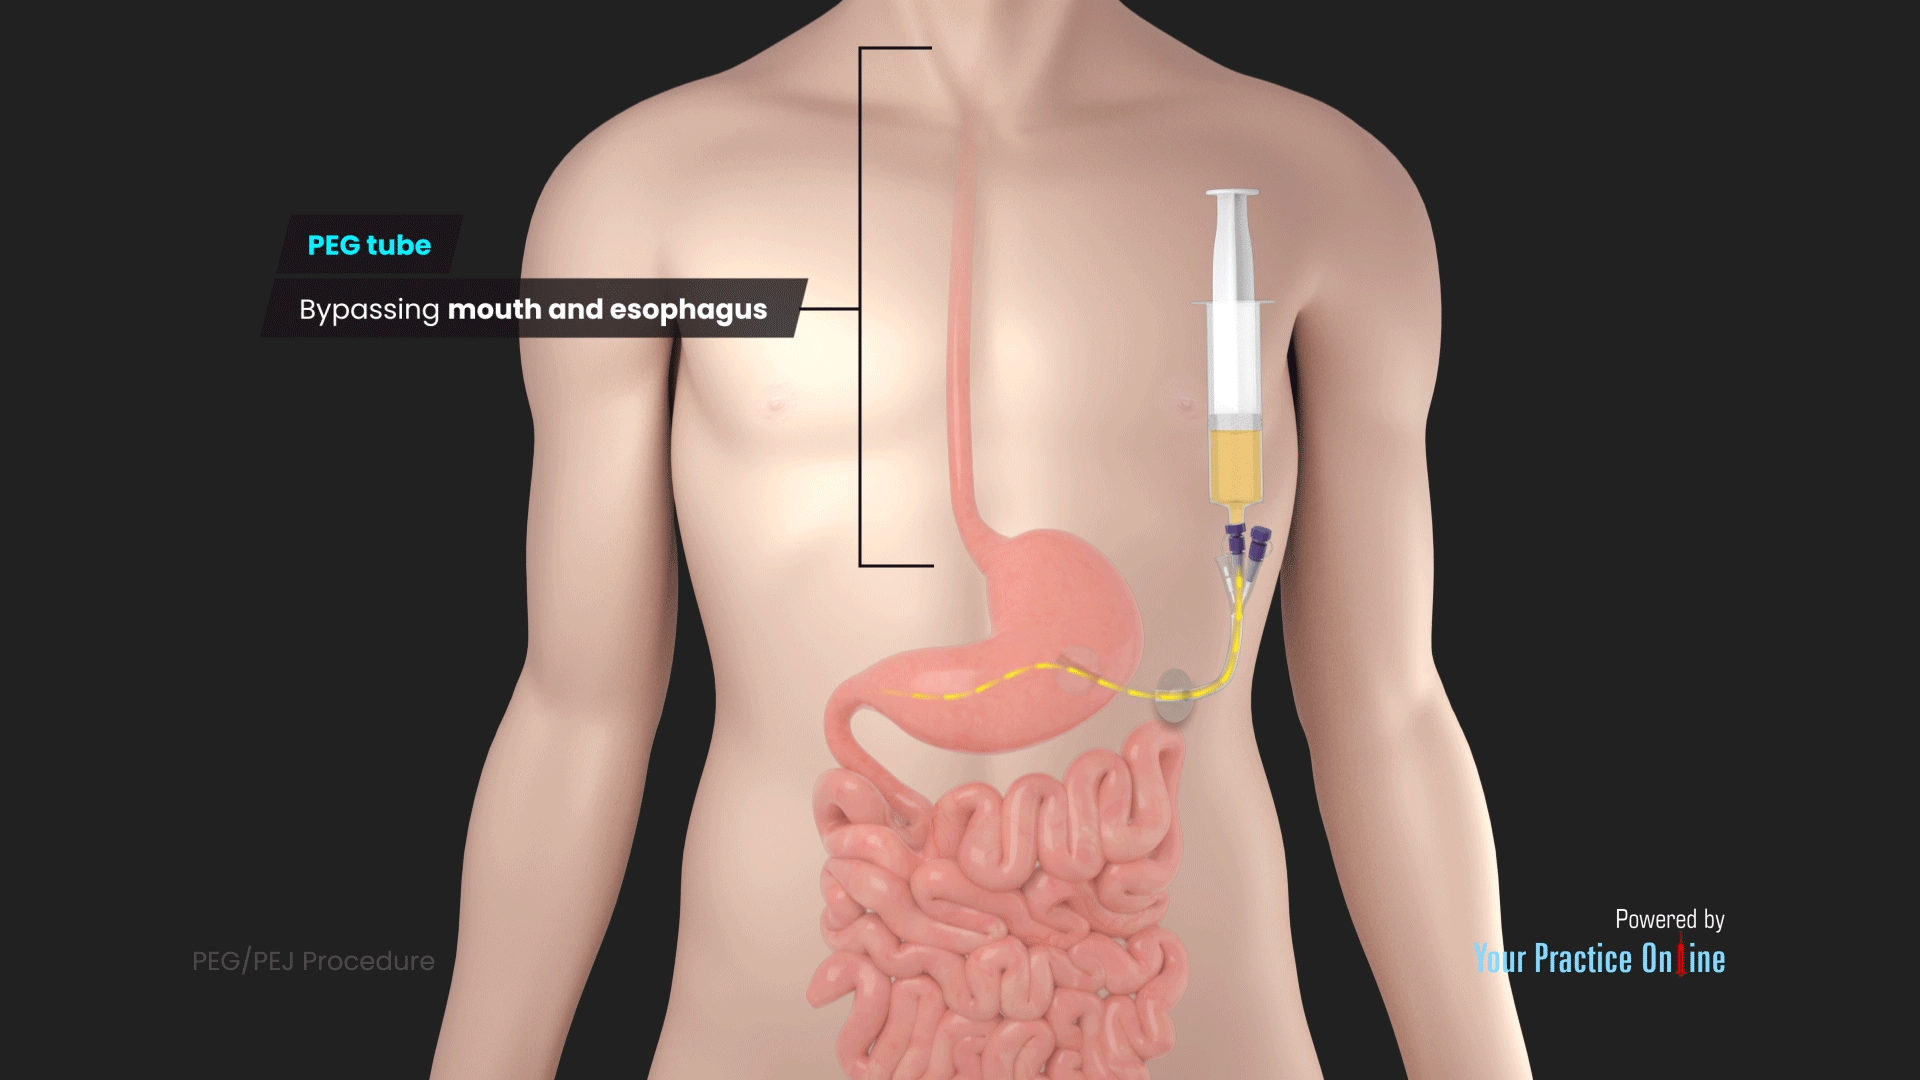

PEG PEJ Procedure Video Medical Video Library

PEG PEG 1 PEG PEG PEG

PEG PEG 1 PEG PEG 1 5cm

1 PEG Point PEG PEG 24 48